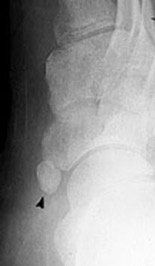

Acccessory navicular

In approximately 10% of the population there is an accessory navicular, or an extra navicular bone. Usually the accessory navicular is not large enough to cause symptoms.

Feet associated with the accessory navicular are usually flat footed, or excessively pronated. The accessory navicular can be prominent causing footwear irritation. The posterior tibial tendon can become overstretched causing degenerative tendinopathy, inflammation of the tendon sheath or irritation between the two fragments of the navicular.